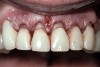

Figure 9  View at 10 weeks post-surgery showing the new gingival level. The preparation and temporary will now be extended to the gingival level.

Figure 9

There are several methods for identifying the correct incisal edge position pre-surgically, including the use of an overlay matrix, altering the contour of the existing teeth using reshaping or bonding, and preparing the teeth and placing temporaries.15 The patient who almost always requires tooth preparation and temporaries in order to correctly identify the incisal edge position is the one with severe wear and a need for the addition of significant length to the incisal edge of the existing teeth. Because there are such significant functional concerns in altering the incisal edge position of these patients, using a simple removable overlay to identify the esthetic position of the incisal edge and gingiva is risky. Instead, it is much more predictable to lengthen the teeth temporarily to evaluate the esthetic and functional success of the new incisal edge position prior to any crown lengthening. If the teeth are amenable to direct bonding to alter incisal edge position, this is often the best approach to temporization. If, on the other hand, the teeth are severely worn and bonding is not realistic, it will probably be necessary to prepare them and place temporaries to evaluate the change. Once it becomes clear that the new incisal edge position is acceptable both esthetically and functionally, the periodontal surgery can be completed to correct gingival levels and, therefore, crown length (Figure 6, Figure 7, Figure 8, Figure 9 and Figure 10).